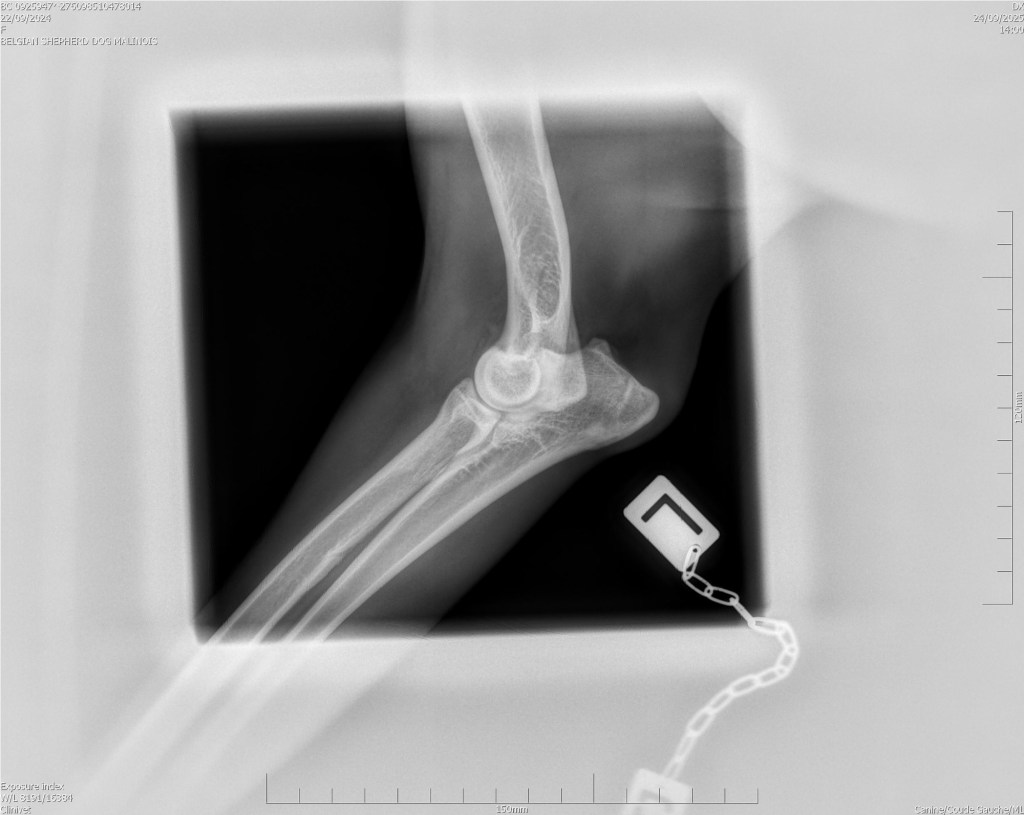

Hips 2/3

Elbows 0/0